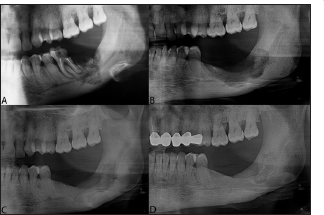

Figure 2: Panoramic radiographs A. Radiograph view demonstrating the medication related to osteonecrosis of te jaw with radiolucent area in the lower left wisdom tooth area and retro molar region B. Post-op 6 months. C. Post-op 2 years D. Post-op 4 years.